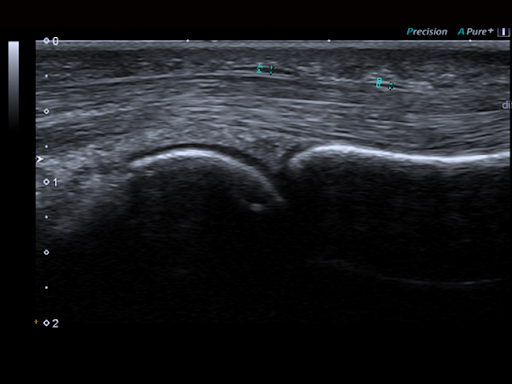

Больше ясности, лучшие клинические результаты

Precision Imaging и ApliPure + обеспечивают исключительно гладкие изображения с заостренным контуром повреждений, улучшенной однородностью изображения и уменьшением помех.

Precision & Aplipure - это передовые технологии визуализации, которые гарантируют, что каждое изображение обеспечивает выдающиеся клинические детали в ближнем или дальнем поле. Резкость границ, уменьшение шума и обеспечение исключительного контрастного разрешения.